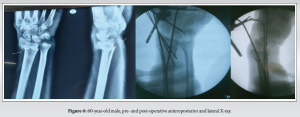

Following administration of anesthesia, the patient was positioned supine with the involved arm extended onto a side support (Fig. 2). The limb was aseptically prepared and draped. Traction was applied, and the fracture was manually reduced. The wrist was adjusted into slight volar flexion and ulnar deviation to facilitate alignment. Once an acceptable reduction was achieved, stabilization was performed using percutaneous K-wires.

The elbow was maintained at 90° flexion. Fracture alignment was confirmed under fluoroscopic guidance, capturing both anteroposterior and lateral views by rotating the C-arm around the wrist while maintaining a steady hand position.

- Post-operative radiographs were taken to assess reduction and fixation quality

Post-operative radiographic assessment revealed an average radial height of 11.15 ± 1.31 mm, radial inclination of 22.40 ± 2.33°, and volar tilt of 10.95 ± 1.83°.